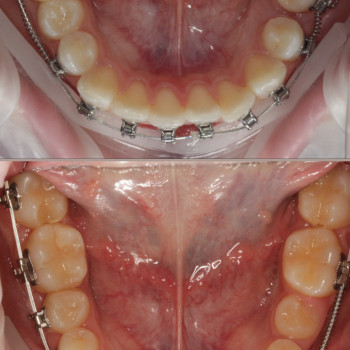

Якщо ти хочеш рівні зуби та красиву посмішку - тобі саме до нас!

Ми зробимо це на високому рівні!

А як саме наважитись на постановку брекетів?

Перший крок - це консультація ортодонта, Ви зможете дізнатись відповіді на запитання які Вас хвилюють. Перед постановкою брекетів усі зубки мають бути здорові, якщо ми бачимо карієс, його потрібно полікувати. Також потрібно зробити рентгенівські знимки для діагностики. За цей час, коли ми готуємо зуби до постановки брекетів, Ви зможете налаштуватись морально, звикнути з думкою що Ваша посмішка засяє новими барвами. На сьогоднішній час носіння брекетів являється престижним!